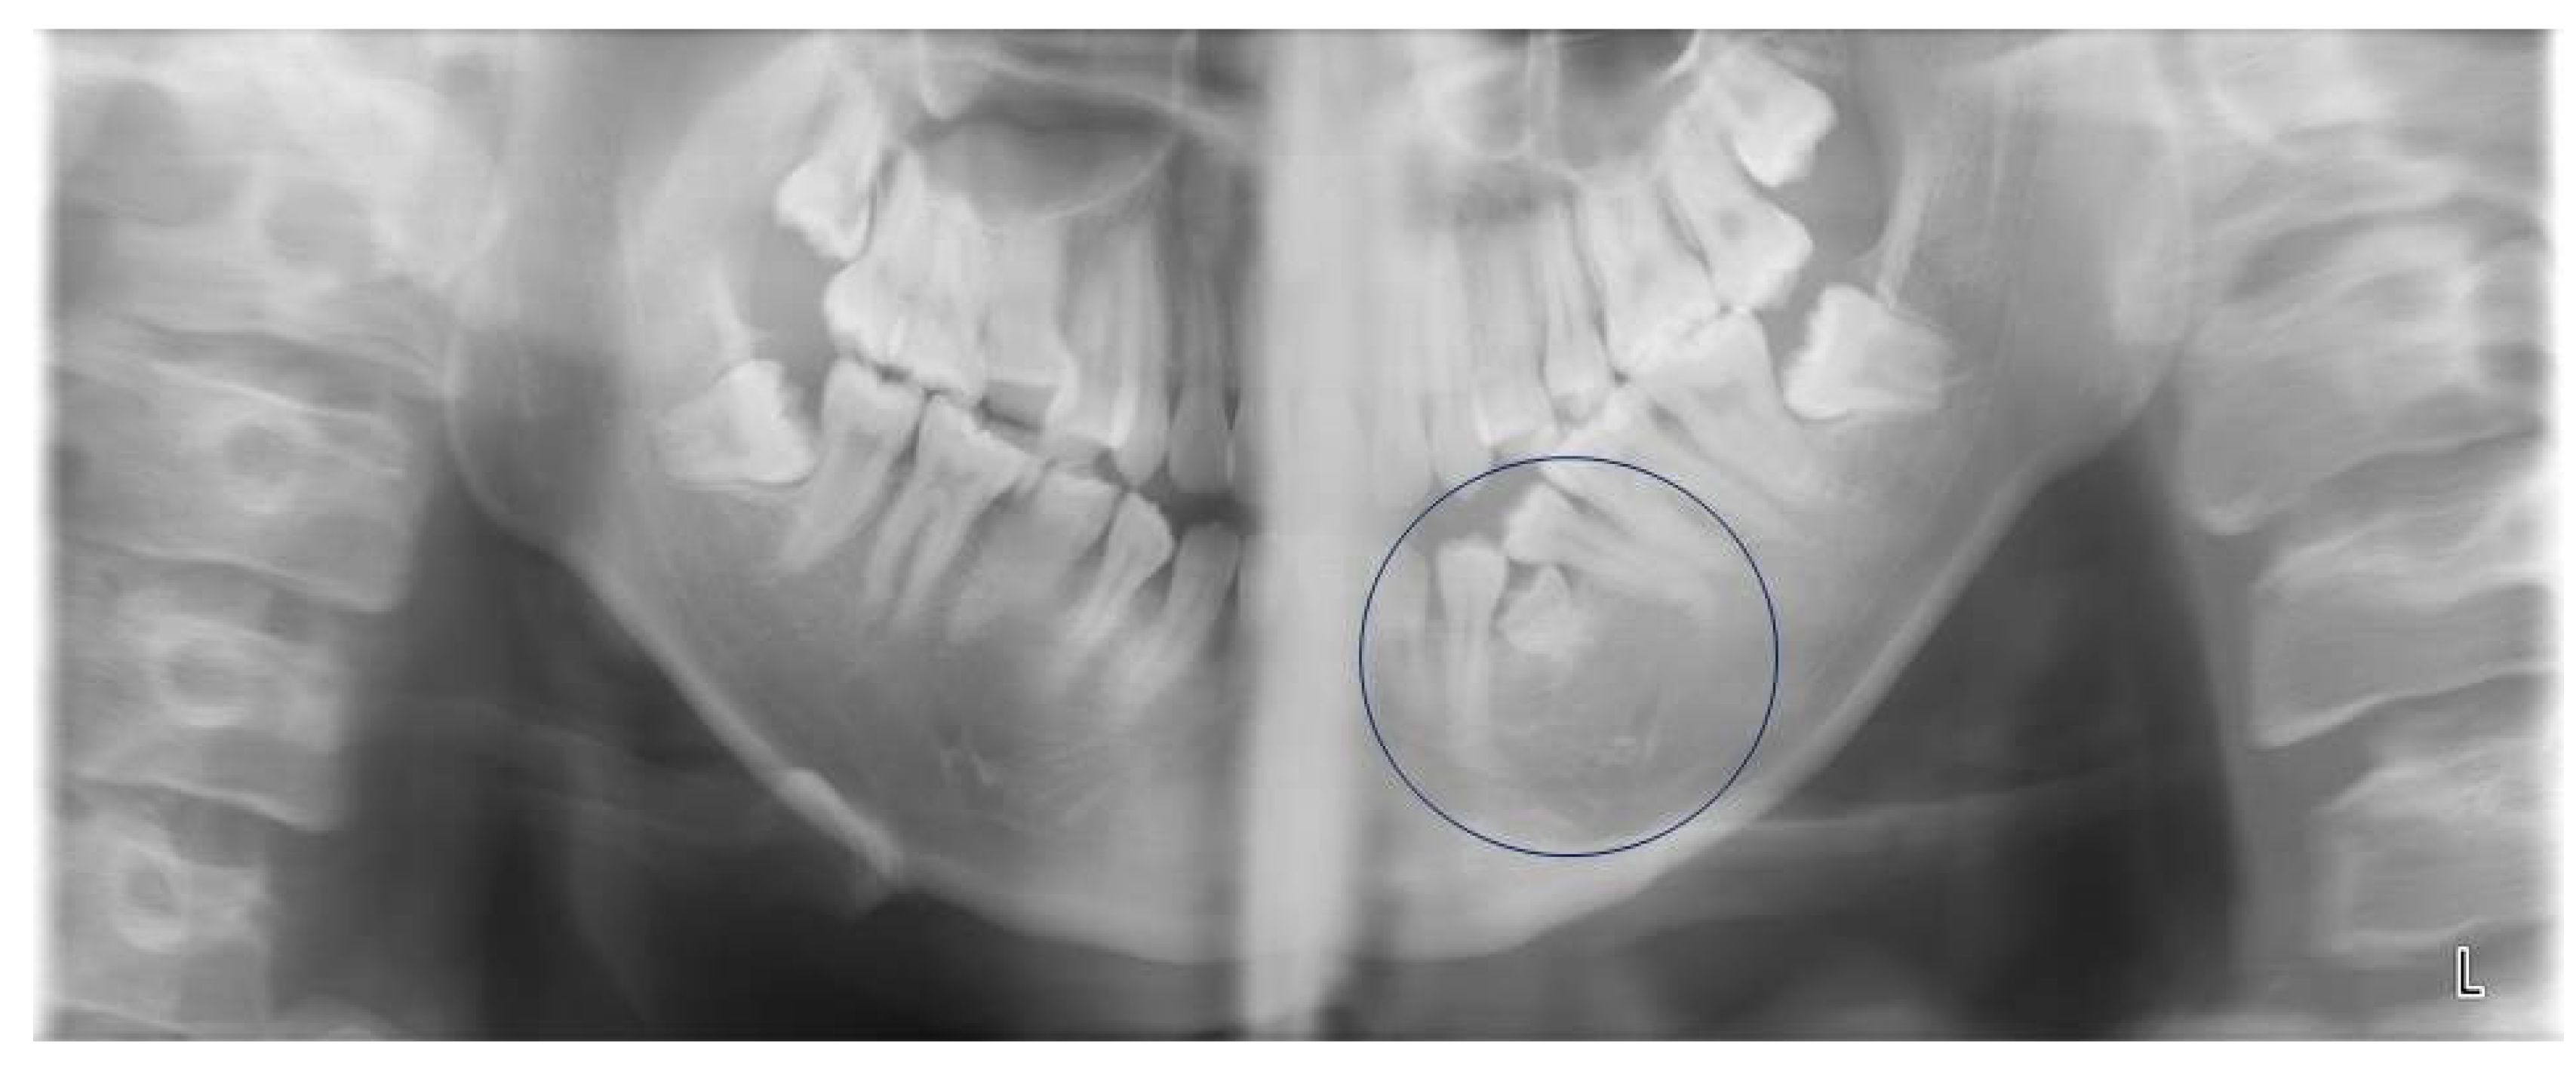

We performed panoramic tomography, with his father and a dentist holding his face and body firmly for stability (Figure 1). We performed this panoramic tomography as we suspected that the cause of his problem might be located deep in the alveolar bone, which would not be revealed by a dental X-ray. The X-ray image showed what looked like the crown of the first deciduous molar in his left mandibular alveolar bone. However, confirmation that it was a submerged first deciduous molar could not be obtained; in any case, it was hard tissue and not an edema.

Figure 1.

Panoramic X-ray image taken at the first visit to Nippon Dental University Hospital. This image revealed the presence of hard tissue between the first and second mandibular premolars (indicated by the circle).